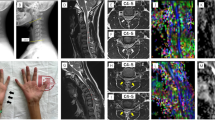

All diffusion images were examined for movement, distortion or eddy current artefacts before analysis. Visible artefacts were present in one patient and one control, subsequently excluded from DTI analysis. Fractional anisotropy (FA), apparent diffusion coefficient (ADC), axial diffusivity (AD) and radial diffusivity (RD) values were calculated voxel-by-voxel using MedINRIA (1.9.0) software (http://www-sop.inria.fr/asclepios/software/MedINRIA). AD describes the principal eigenvector (λ1) and RD the mean of the remaining two eigenvectors perpendicular to λ1 (λ2 + λ3/2) [23]. Regions of interest (ROIs) covering the entire spinal white and grey matter were drawn on b0 images (axial views). ROIs included (1) the lateral part and (2) the medial part of the spinal cord on both sides (Fig. 2c). The lateral ROI was defined so as to include the lateral corticospinal tract (CST) and the medial ROI was defined as the remaining part of the spinal cord (e.g. Fig. 2c–e) [19].

Diffusion tensor imaging and spinal stenosis in cervical spondylosis patients without conventional MRI findings of spinal cord damage. a, b Left: Sagittal T2-weighted images showing cervical spinal cord anatomy and fibre tracking in a control subject (top) and a cervical spondylotic myelopathy (CSM) patient (bottom; patient 7 in Table 1). Note the presence of spondylotic stenosis at C4–C5 and C5–C6 (arrow) levels in the patient. Right: fibre tracking shows ascending and descending spinal cord fibres (green craniocaudal FA direction) in both subjects. c Axial b0 image illustrating positioning of medial (M) and lateral (L) ROIs. d, e Axial view at C5 level of FA map with lateral and medial spinal cord ROIs in a healthy control (top) and a patient (bottom; same subjects as in a, b). f Pavlov’s ratio (mean ± 95 % confidence intervals) was lower in patients than controls at all levels (C2–C5) indicating reduced spinal canal space in CSM patients. *Significant post hoc comparisons. Open circles controls, black triangles cervical spondylosis patients

To limit the partial volume effect (i.e. inclusion of voxels containing cerebrospinal fluid, CSF) we verified that ROI placement on the b0 image did not contain voxels extending into CSF (voxels covering both were removed). Only voxels with diffusion predominantly in the craniocaudal direction on FA colour maps were included. Two raters (PL and FO) separately performed ROI measurements, and reliability of DTI parameters within these ROIs were evaluated using intraclass correlation coefficients (ICC). ICC > 0.7 was considered to reflect good reliability. Deterministic tractography using DTItrack (MedINRIA software, with FA > 0.2) with seed regions covering whole spinal cord at C2 and C5 levels was used to ensure anatomical correspondence between tracked fibres and T2-weighted images.

Anatomical MRI showed signs of cervical spinal canal stenosis in 13 (81 %) patients and in four (20 %) controls. None of the patients had signs of spinal cord compression. Patients also showed more signs of herniated discs than age-matched controls (Table 2). In patients, stenosis was most frequent at C5–C6 (81 %) followed by C4–C5 (44 %, example Fig. 2b). Quantification of stenosis according to Pavlov’s ratio showed the same pattern with the majority of patients showing lowest ratios (least canal space) at C5 (69 %). Three patients (19 %) had lowest ratio at C4 and two patients (12 %) at C3. ANOVA comparison of groups showed lower Pavlov ratios in patients than controls (GROUP: F = 13.4, p < 0.001; Fig. 2f). Post hoc tests showed diminished spinal canal space at all cervical levels in patients (p < 0.05).

Diffusion parameters

All subjects showed good quality FA, FAdir maps and fibre tracking from C1 to C5 (examples Fig. 2). Inter-rater reliability was good for FA, ADC, AD and RD (ICC 0.93, 0.94, 0.98 and 0.75, respectively), without systematic bias between raters (paired t test, p > 0.1). Whole spinal cord ROIs included a similar number of voxels in patients (40 ± 8) and controls (41 ± 8, P = 0.64), as did lateral spinal cord ROIs (8 ± 1 voxels in patients and 9 ± 2 voxels in controls, P = 0.84).

ANOVA across all spinal levels (C1–C5) showed an effect of ROI and LEVEL on all parameters, consistent with previous studies [19, 25, 26]. FA was greater in the lateral than in the medial spinal cord (ROI: F = 62.9, p < 0.001) and higher at C1–C3 compared to C4–C5 (LEVEL: F = 13.4, p < 0.001). ADC was reduced in the lateral ROI (ROI: F = 68.9, p < 0.001) and lower at higher cervical levels (LEVEL: F = 9.3, p < 0.001). Patients and controls both showed this pattern and groups were similar in all parameters when analysed across all spinal levels. However, when confining the ANOVA to the level of greatest stenosis significant group differences were found. FA was reduced in patients (GROUP: F = 4.1, p = 0.05) and differed between lateral and medial ROIs (GROUP*ROI, F = 9.9, p = 0.004). Post hoc comparison showed a significant reduction of about 9 % in the lateral ROI only (p = 0.003, Fig. 3a). RD showed an inverse pattern tending to be increased in patients and regionally different (GROUP: F = 3.9, p = 0.06; GROUP*ROI: F = 3.7, p = 0.06). Post hoc tests showed a 16 % increase in RD confined again to the lateral ROI (p = 0.02, Fig. 3d). ADC and AD showed no GROUP differences (Fig. 3b, c). The five subclinical patients showed the exact same group differences (p < 0.05).

Regional spinal DTI parameters of lateral and medial spinal cord across C1–C5 levels and at the level of greatest stenosis. a FA (mean ± 95 % confidence intervals) was lower in patients in the lateral spinal cord, only at the level of greatest stenosis (p = 0.003). No significant difference in FA was found in the medial spinal cord. b Patients had similar spinal ADC values as controls in both whole spinal cord and regionally at the level of greatest stenosis. c Axial diffusivity (AD) was also comparable across groups. d RD was higher in the lateral spinal cord in patients at the level of greatest stenosis only (p = 0.02). Open circles controls, black triangles cervical spondylosis patients, *significant group differences